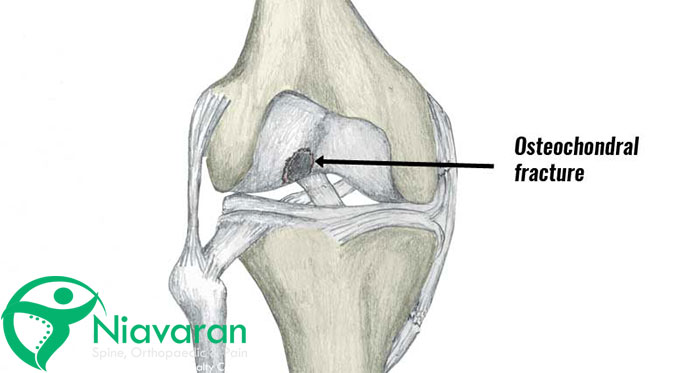

استئوکندرال زانو یک بیماری مفصلی است و زمانی رخ میدهد که استخوان از غضروف جدا شده و شروع به مردن کند. این بیماری معمولا به دلیل کمبود جریان خون در استخوان ایجاد میشود. هنگامیکه قطعات کوچک استخوان و غضروف جدا شده و شروع به شکستن میکنند، باعث ایجاد درد میشود.

استئوکندرال وضعیتی است که در آن کمبود خون به مفصل، باعث نرمشدن استخوان میشود. این عارضه باعث میشود که یک قطعه کوچک از استخوان مرده و از استخوان بزرگتر جدا شود. این قطعه استخوان همراه با غضروفی که استخوان را میپوشاند و از آن محافظت میکند، ترک میخورد و شل میشود.

احتمالا استخوان شل و غضروف در جای خود باقی بمانند، یا میتوانند با مفصل حرکت کنند که موجب مفصل ناپایدار خواهد شد. این بیماری، ضایعهای را در جایی که استخوان و غضروف جدا میشوند، به جا میگذارد. کل فرآیند استئوکندرال احتمالا ماهها یا حتی سالها طول بکشد و حتی علائم آن مدت زیادی زمان ببرد تا ظاهر شود.

اگرچه استئوکندرال میتواند هر مفصلی را درگیر کند؛ اما در 75 درصد موارد، زانو را درگیر میکند. استئوکندرال معمولا زانو را در انتهای استخوان ران (فمور)، مچ پا و آرنج درگیر خواهد کرد. این عارضه میتواند در سایر مفاصل از جمله شانه و لگن هم رخ دهد. به ندرت استئوکندرال در بیش از یک مفصل ظاهر شود. افرادی که به این حالت مبتلا هستند، معمولا قد کوتاهی دارند.